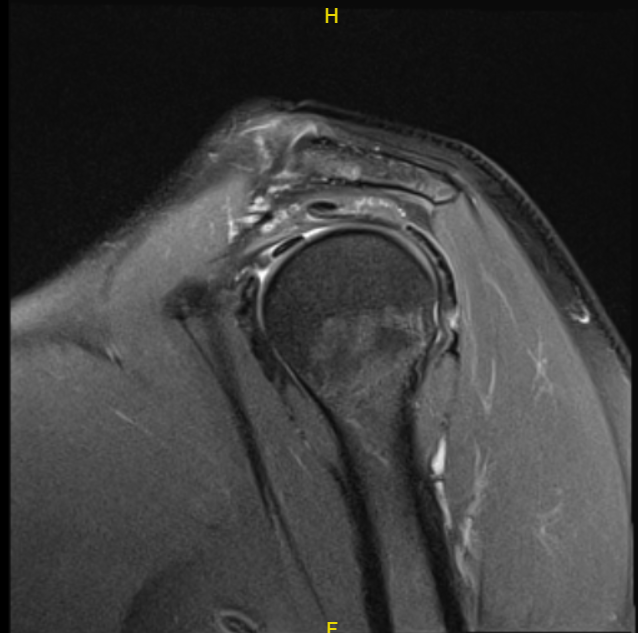

The patient presented an MRI result that showed multifocal rotator cuff tendinosis with a delaminating high-grade partial-thickness intrasubstance insertional tear at the confluence of the supraspinatus and infraspinatus tendons.

Mild tendinosis of the intra-articular portion of the biceps tendon. Mild degeneration with fraying/tearing at the base of the superior labrum. Very mild acromioclavicular joint arthrosis. Mild subacromial-subdeltoid bursitis.

MRI-3T left shoulder non-contrast